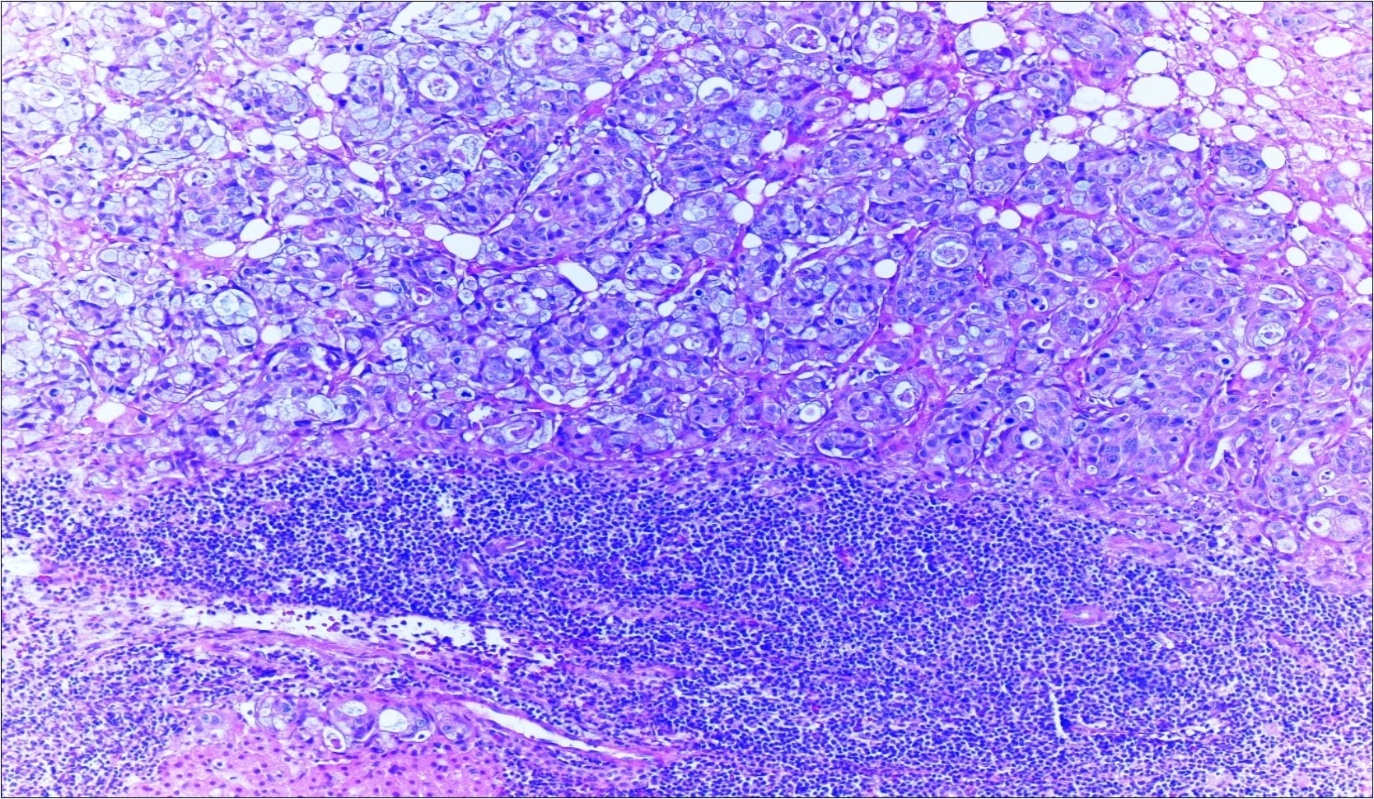

A 63-year-old woman presented to the Department of General Surgery as an outpatient with abdominal pain. Physical examination showed the signs of acute appendicitis and appendectomy was performed. During microscopic examination, a small focus of atypical monotonous lymphoid cell population was seen and the material was sampled totally. The pathological examination revealed MALT lymphoma (Figure 1), with diffuse positivity of cluster of differentiation (CD) 20 (Figure 2), CD 79a and B-cell lymphoma (Bcl- 2) (Figure 3) with just a few CD3 positive lymphoid cells. However, no evidence of adenocarcinoma was found in the appendectomy specimen. After the diagnosis of lymphoma, a complete colonoscopy was planned and this revealed a solid tumoral mass in the caecum measuring 5x4x4 cm. Computed tomography of the abdomen and pelvis revealed mesenteric lymphadenopathy associated with a mass in the caecum with multiple nodules in liver consistent with metastasis (Figure 4). Frozen sections were not obtained since the treatment method would not be affected. The patient underwent anterior resection with regional lymphadenectomy, with the pathological assessment of the resected specimen revealing a collision tumor consisting of a poorly differentiated adenocarcinoma extending through the muscularis propria with MALT lymphoma (Figure 5). Microscopic evaluation of the 11 regional lymph nodes in the mesentery of the resected colon and liver biopsy showed diffuse infiltration of MALT lymphoma with metastasis of adenocarcinoma (Figure 6). According to immunohistochemistry, atypical lymphocytes were positive for CD 20, Bcl-2, and negative for CD3, CD5, CD10, CD23, Bcl-6, terminal deoxynucleotidyl transferase, and cyclin D1. The proliferation fraction (MIB-1 immunostaining) was approximately 20%. The morphological and immunohistochemical findings were used to confirm the diagnosis of synchronous presentation of MALT lymphoma and colon adenocarcinoma within the caecum, mesenteric lymph nodes and liver metastases.

Figure 4.Adenocarcinoma with MALT lymphoma infiltration of liver (h&e;200)

Figure 5.Adenocarcinoma with MALT lymphoma infiltration of colon (h&e;200)